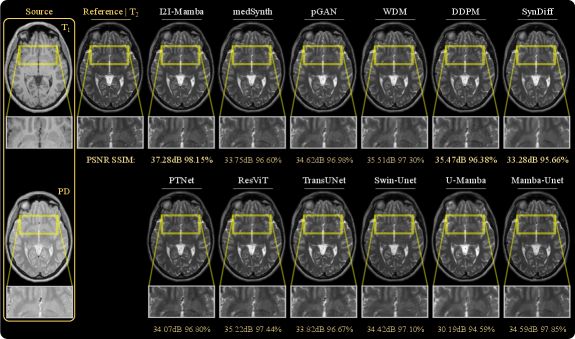

Synthetic target images from representative tasks are displayed in Fig. 3 for IXI, and in Fig. 4 for BraTS. Among competing methods, convolutional baselines suffer from residual noise (e.g., pGAN) or structural inaccuracies (e.g., medSynth, WDM); diffusion baselines suffer from inaccurate depiction of low-to-moderate contrast tissue structures (e.g., DDPM) or a degree of spatial blur (e.g., SynDiff); and transformer and SSM baselines suffer either from a degree of spatial blur and contrast loss (e.g., PTNet, U-Mamba, Mamba-UNet) or pixel intensity artifacts (ResViT, TransUNet, Swin-Unet) that lead to inaccuracies in depiction of detailed anatomical structures. Particularly evident in BraTS images containing pathology, baselines generally suffer from hallucinatory features manifesting as hypo-intense or hyper-intense signals deviating from ground truth. In comparison, I2I-Mamba synthesizes target images with more accurate depiction of detailed structure and contrast in tissues, along with lower artifacts.

Performance benefits of I2I-Mamba over SSM baselines can be attributed to the fundamental architectural differences between methods. Note that U-Mamba and Mamba-Unet follow a UNet-style architecture that substantially lowers spatial resolution of encoded feature maps, and they use conventional image-domain SSM operators based on raster-scan trajectories. In contrast, I2I-Mamba adopts a residual architecture where the bottleneck maintains relatively higher-resolution semantic representations, and it uses ddMamba blocks operating in image and Fourier domains, equipped with SSM operators based on spiral-scan trajectories. Our results indicate that these technical elements enable I2I-Mamba to sensitively capture of a comprehensive set of contextual features to synthesize high-quality target images in multi-contrast MRI protocols.